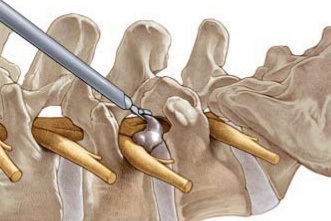

脊柱内镜摘除突出的椎间盘示意图

直径5mm内镜摘除大块突出的椎间盘组织

脊柱内镜90年代在美欧起步,2006年国内引入现代内镜,经过15年的发展,国内脊柱内镜的应用范围和技术发展都处于世界领先水平。常规腰椎间盘突出,腰椎管狭窄都能解决。7mm小洞,精准减压,符合外科内镜化的趋势,就如普外科腹腔镜、胸外科胸腔镜一样;更可以结合手术机器人,实现智能化、精准化。病人术后第2天下地,损伤小,恢复快;尤其是对年轻人和老年人优势更明显,不像做开放手术,对全身影响很小,病人耐受性好。随着不断探索发展,脊柱内镜的应用范围也已逐步向颈椎、胸椎、全脊柱拓展,向骨折、肿瘤的减压、脊柱融合术等全病种拓展。